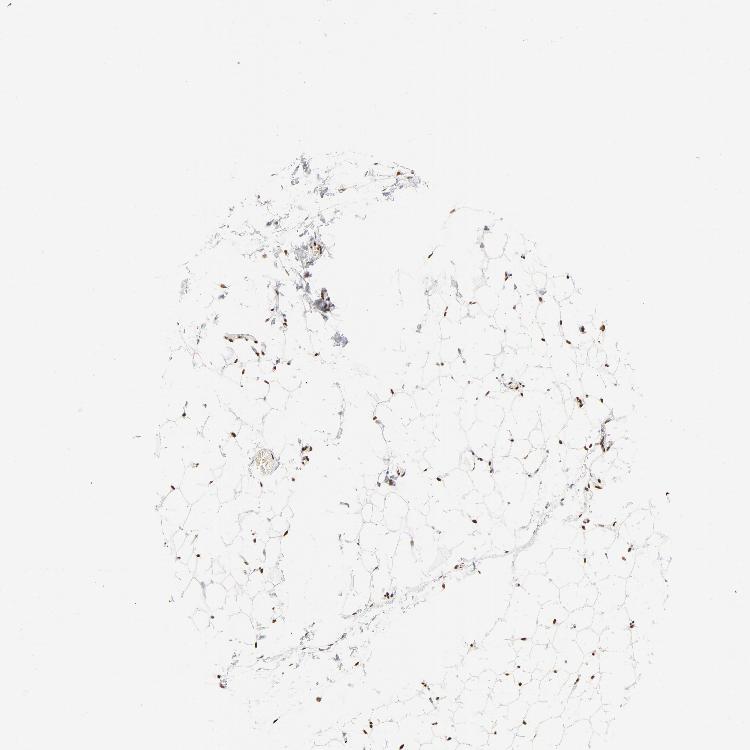

SOFT TISSUE 2 - Antibody stainingi

Antibody staining in the annotated cell types in the current human tissue is reported as not detected, low, medium, or high, based on conventional immunohistochemistry profiling in selected tissues. This score is based on the combination of the staining intensity and fraction of stained cells.

Each image is clickable and will lead to virtual microscopy that enables deeper exploration of all samples and also displays staining intensity scores, fraction scores and subcellular localization as well as patient and tissue information for each sample.

Antibody HPA017284Antibody CAB003703

Fibroblasts Medium-

Peripheral nerve LowHigh